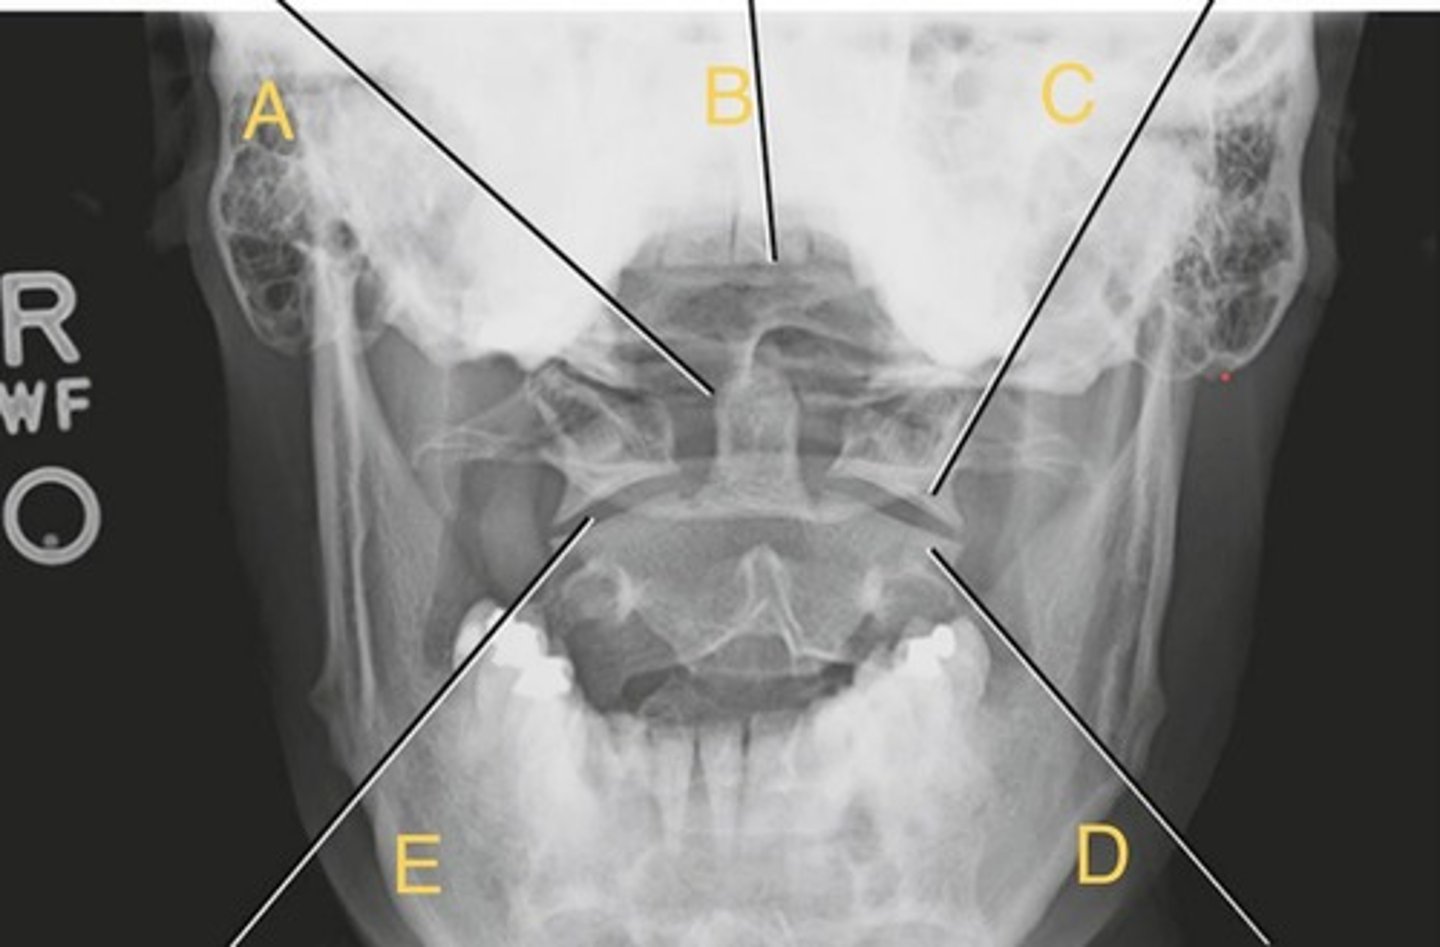

odontoid process

A.

Upper incisor

B.

C1 lateral mass

C.

C2 body

D.

C1-C2 - atlantoaxial joint

E.

Open mouth

What position?